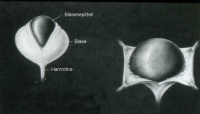

Der künstliche Harnblasensphinkter besteht aus einer auffüllbaren Manschette, die in die um die Harnröhre gelegt wird, einem Flüssigkeitsreservoir sowie dem dazugehörigen Schlauchsystem (Abbildung 14).